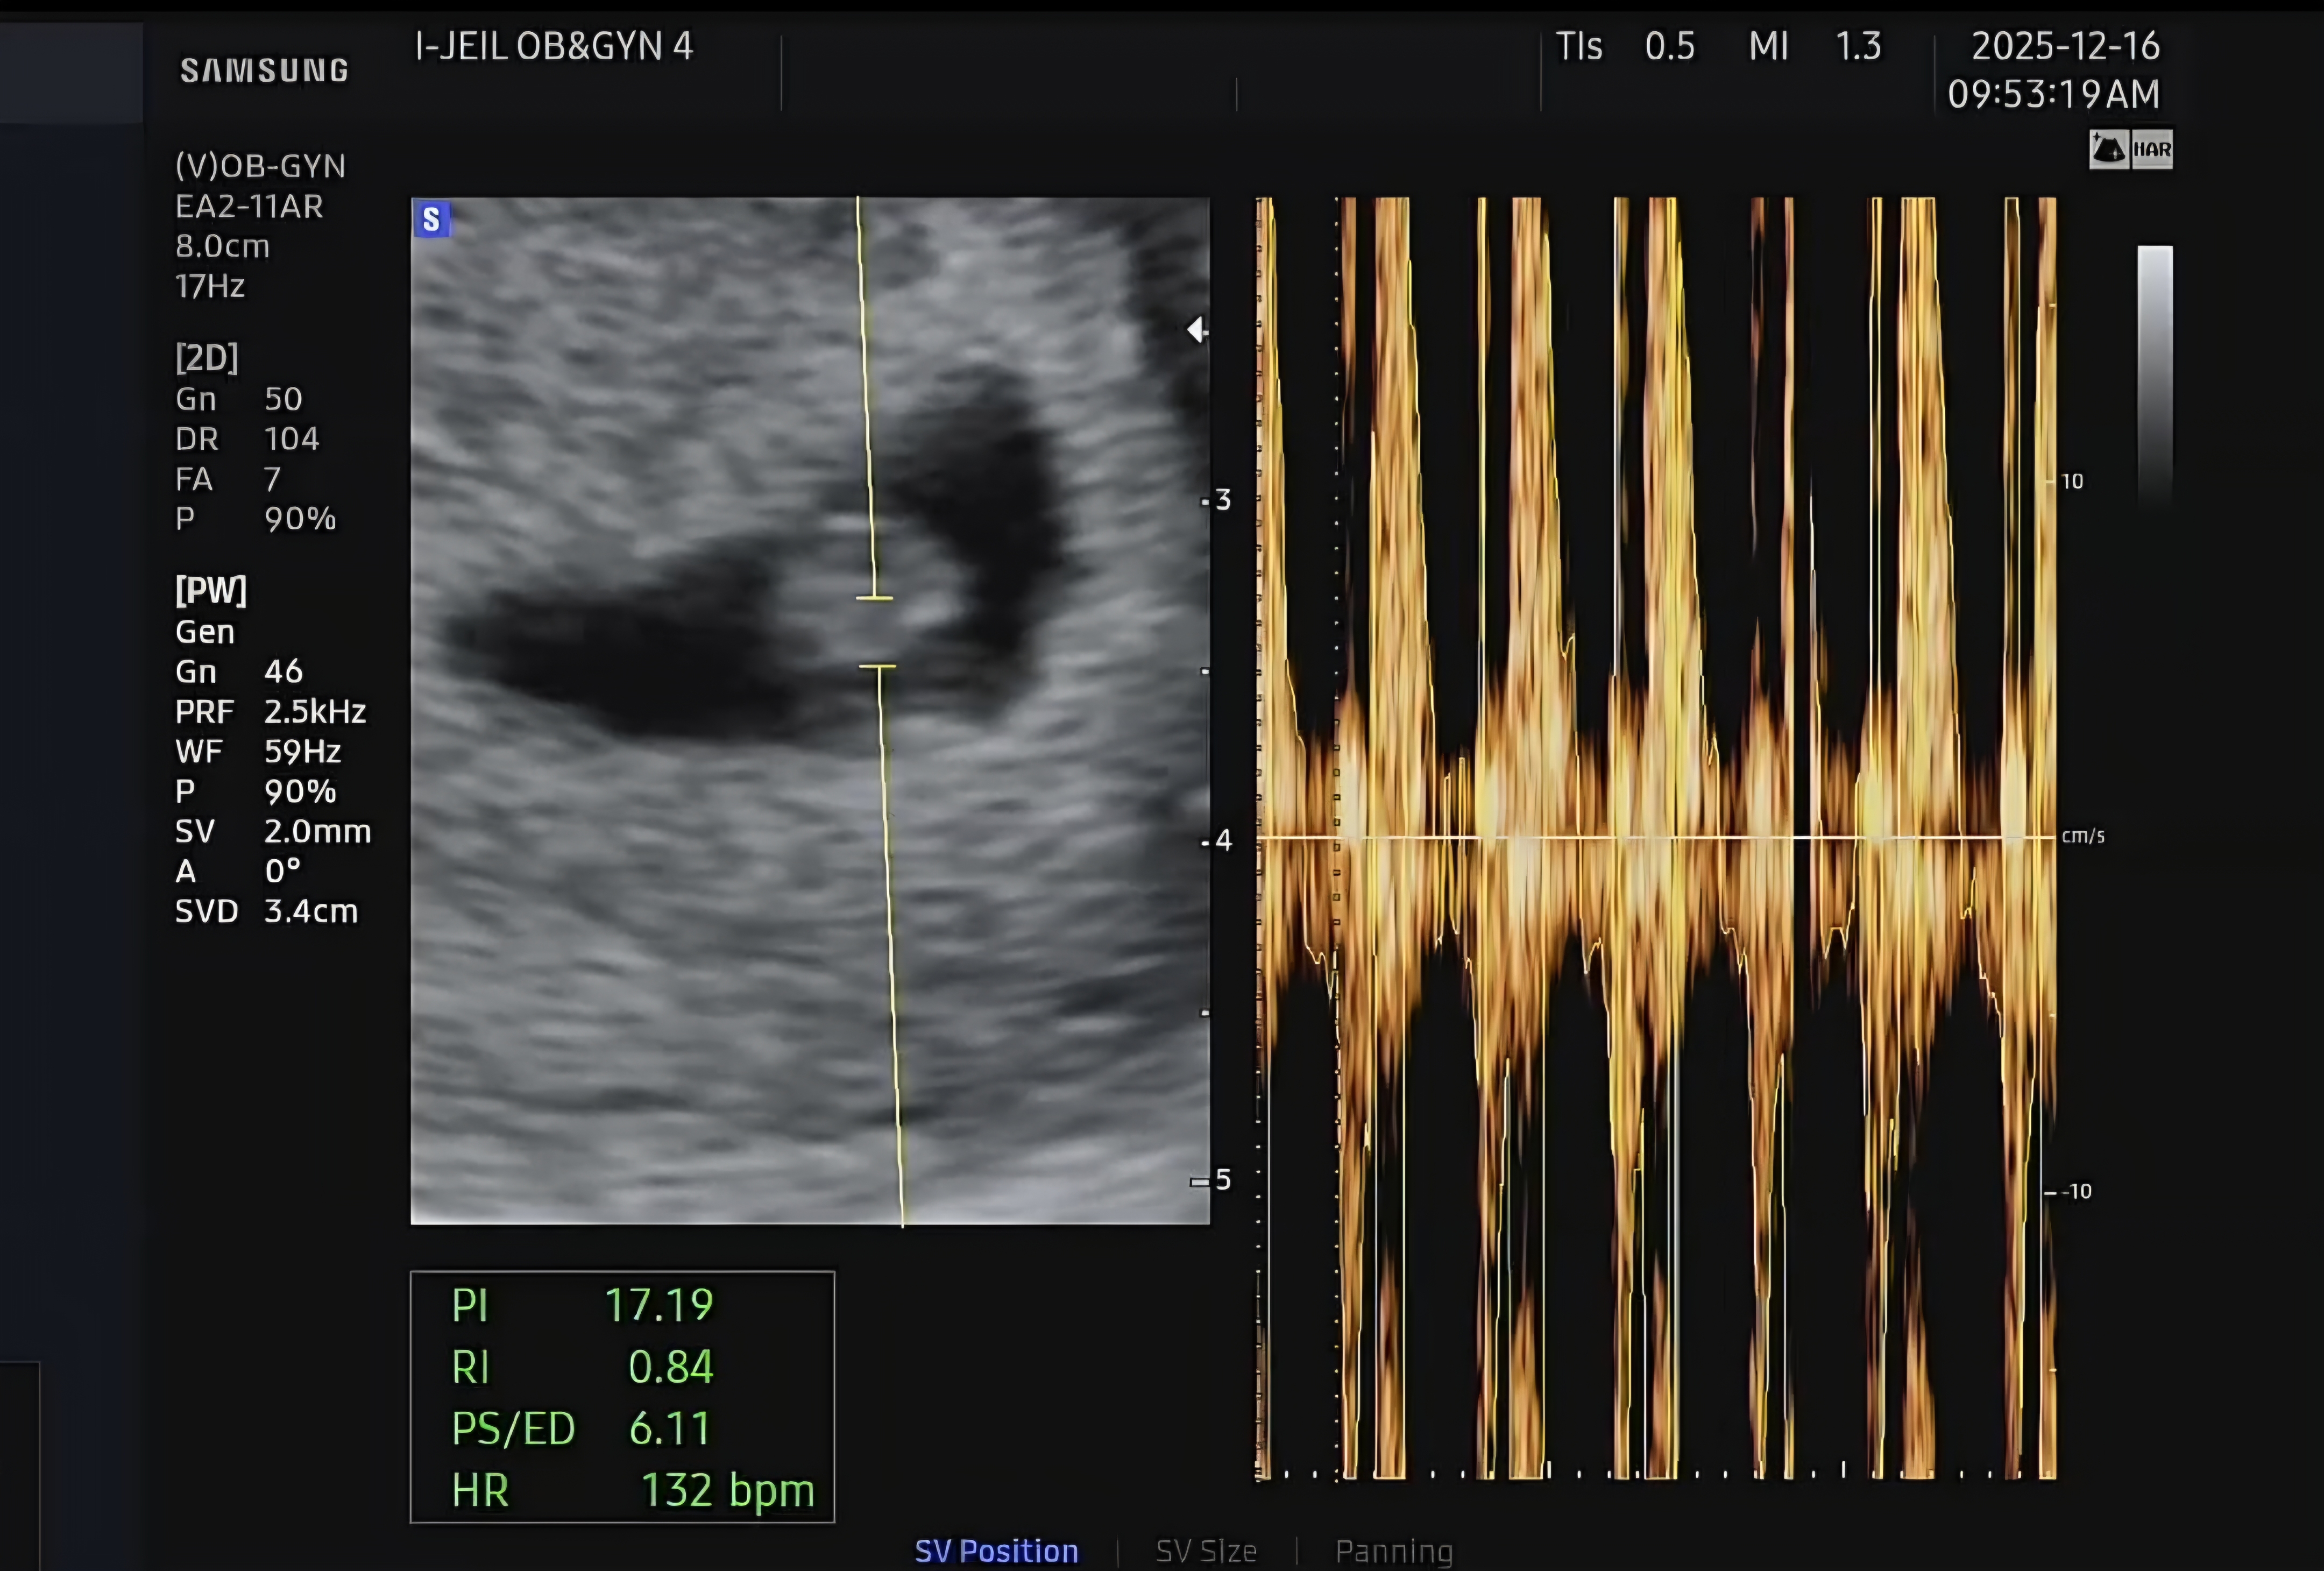

4주5일차에 아기집보고 2주를 열심히 기다려서 6주5일차 오늘 심장소리 듣고왔어요~ 0.81cm인데 심장이 130이상 뛰는게 신기하네요ㅎ 뭐랄꺼 생각보다 감동이다 그런 느낌은없고 아직도 잘 안믿겨요.. 내 몸 속에 심장이 뛰는 아이가있다니! 이번주 주말엔 산후조리원 투어갑니다~ 제미나이가 서울은 6주에서 8주사이에 해야한다는데..너무 이른거 아닌가 싶긴하네용~ 다들 산후조리원 투어 언제가셨나요? 뭘 확인해야하고 물어봐야할지 잘모르겠네요ㅎㅎ 꼭 확인해야할게있으면 팁 부탁드립니다ㅎㅎ